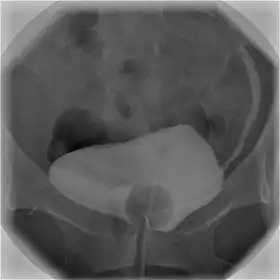

![]() تصویر سیستوگرافی که وجود ماده حاجب در مثانه و حالب چپ (در سمت راست تصویر) را نشان میدهد. | |

با استفاده از کاتتر ادراری، کنتراست(ماده حاجب) رادیویی در مثانه تزریق میشود و تصویربرداری اشعه ایکس انجام میگیرد. از سیستوگرافی میتوان برای ارزیابی سرطان مثانه، ریفلاکس وزیکویورترال، پولیپ مثانه و هیدرونفروز استفاده کرد. این روش نسبت به CT لگن به اشعه کمتری نیاز دارد، اما حساسیت و اختصاصیت آن کمتر از MRI یا CT است. برای ارزیابی مقدار ادرار باقیمانده در مثانه در بزرگسالان، بیمار ۳ مرحله ادرار کرده و تصویربرداری انجام میشود، که برای ارزیابی اختلال عملکرد انقباض مثانه مفید است. گاهی یک رادیوگرافی نهایی نیز از کلیهها پس از اتمام مراحل مذکور برای ارزیابی رفلاکس وزیکویورترال مخفی انجام میگیرد. [1]